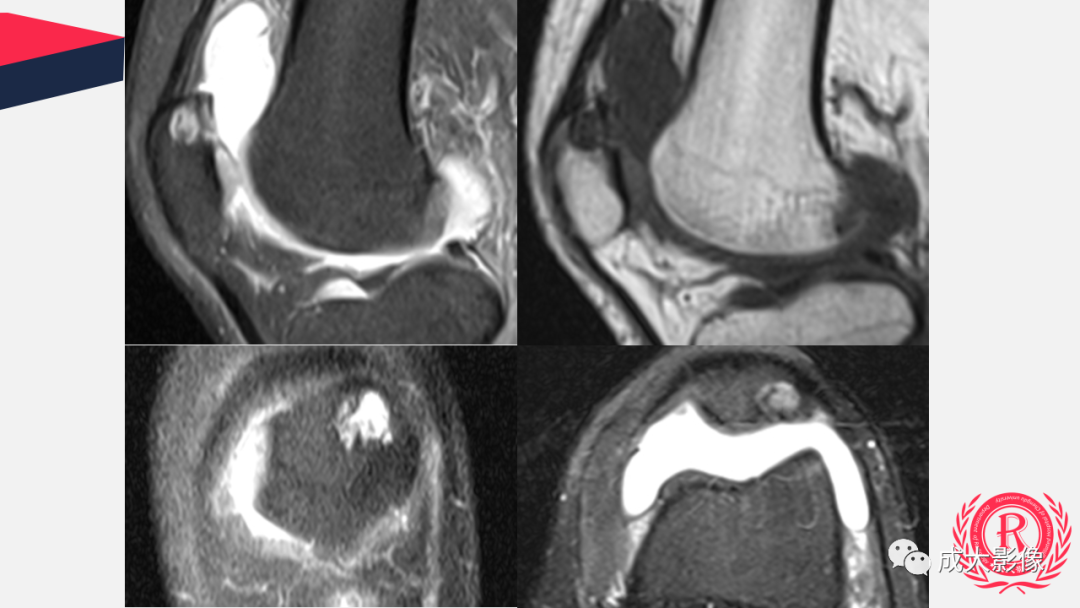

【PPT】剥脱性骨软骨炎

病例: